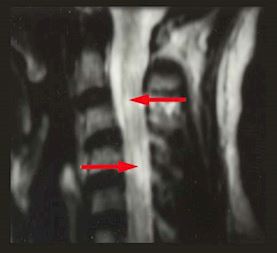

MRI Results

Spinal Cord

Arrows point to plaques or areas of demyelination